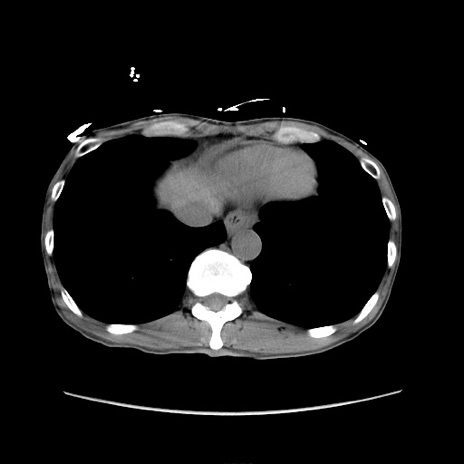

症例

冠状断像